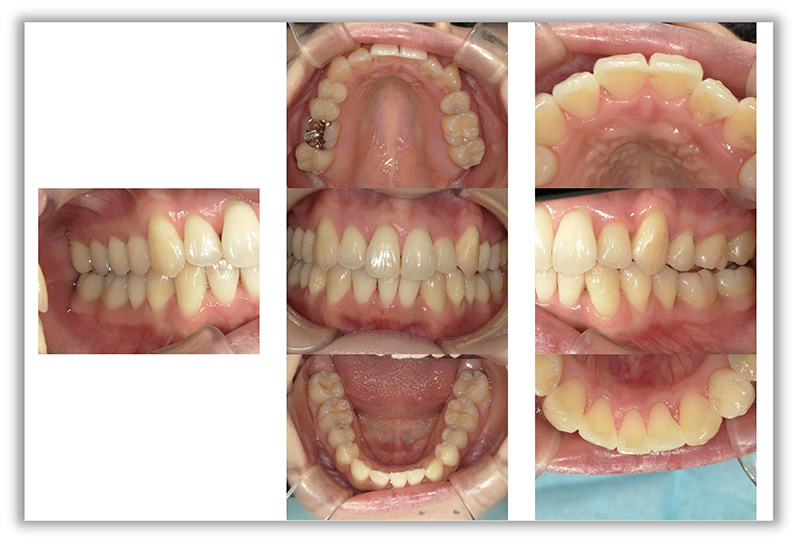

CASE_04

50代女性(インビザライン矯正+セラミック治療)

- 患者さん情報(年齢・性別)

- 50代 女性

- 主訴

- 歯並びが気になる、被せものがとれている

- 治療箇所

- インビザライン、セラミック4か所

- 治療方法

- インビザライン、セラミック治療

- 費用

- インビザライン66万円、セラミック治療22万円

- 治療期間

- 約4年

- その治療によるリスク・副作用

- 保険が効かない

- 歯肉退縮することがある

- 矯正中はしみたり、痛みを伴うことがある

- 患者様の声